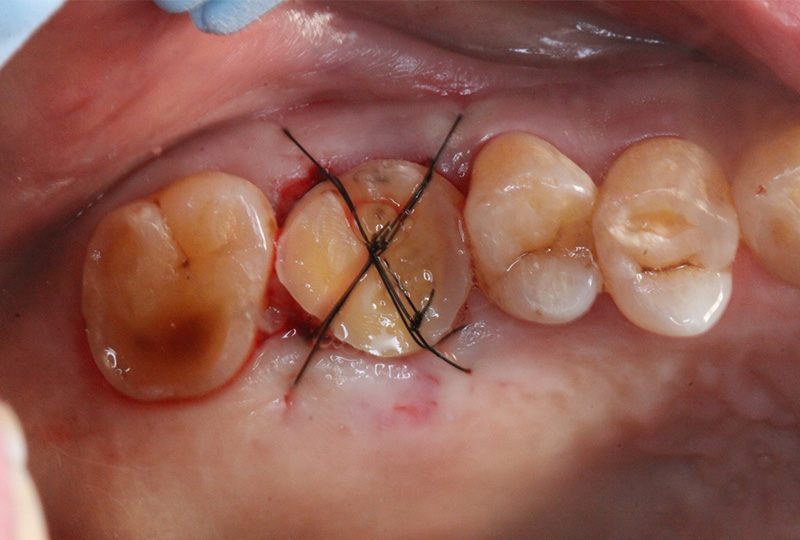

『歯のひび(歯根破折)』など通常であれば抜歯と言われるような歯の保存や歯を失った所に親知らずなどを移動させる『歯の移植』など一般の歯科医院では行わない特殊な治療も行なっております。